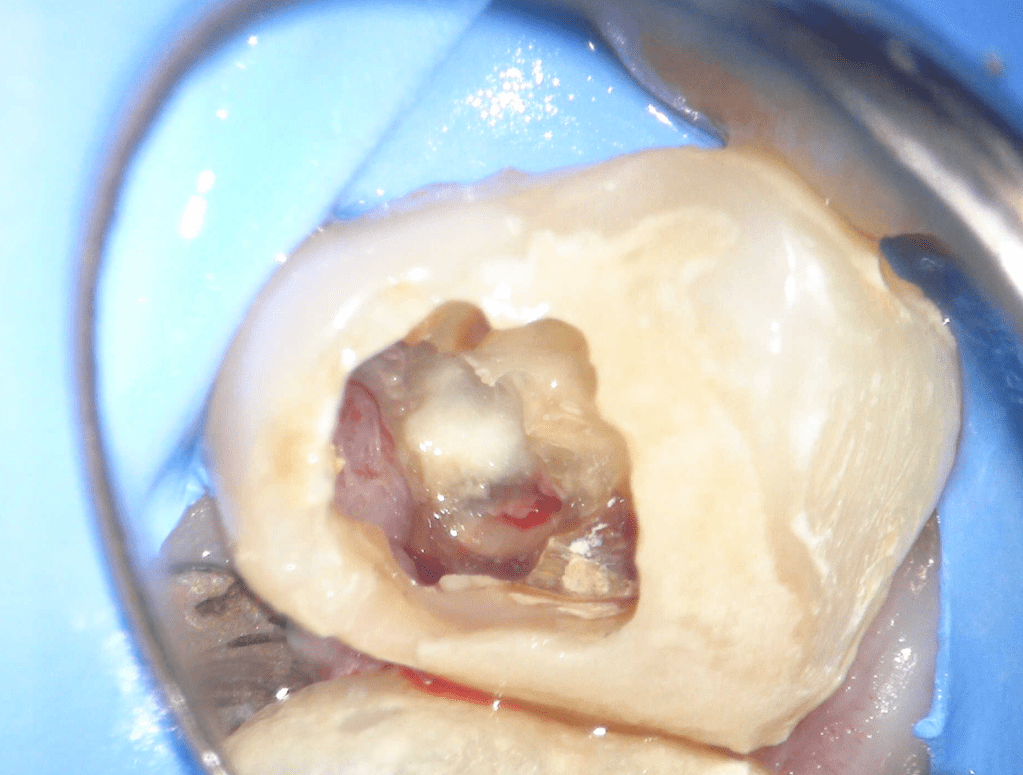

Pulpotomía biodentine + reco preendio